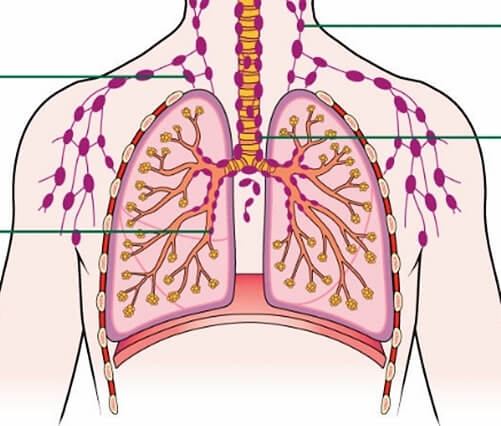

TNM에서 T 다음 적혀있는 N은 'Lymph node' 의 앞글자 이며, 이는 '림프절'을 뜻하는 말입니다. 즉, 폐암이 림프절로 얼마나 전이를 했는지를 나타내는 것을 뜻합니다.

우리 몸에 산소를 공급하는 과정에서 수많은 세균들과 이물질들이 폐에 침범합니다. 그래서 이러한 세균들을 막기 위해서 폐에는 광범위하게 전체적으로 림프절이 분포되어 있습니다. 위에 사진을 보시면 됩니다. 그래서 N은 이렇게 폐에 분포되어 있는 림프절로 폐암이 얼마나 전이 됐는가를 구분하는 것입니다.